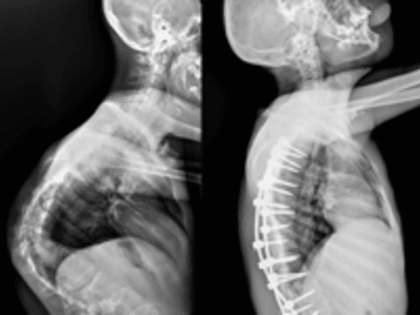

Российские хирурги провели уникальную операцию мальчику с редчайшим генетическим заболеванием

Врачи отделения травматологии и ортопедии РДКБ РНИМУ им. Н.И. Пирогова Минздрава России провели успешную операцию по коррекции кифосколиоза у пациента с синдромом Протея.